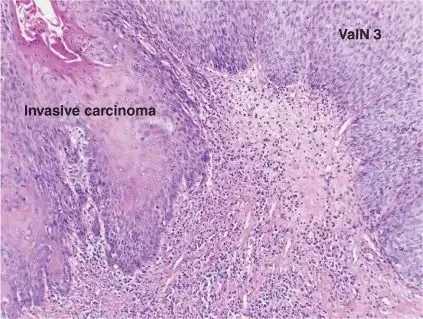

- Squamous cell carcinomas that begin in the epithelial lining of the vagina account for about 85% of vaginal cancers occur in women( 50 yrs and up).

- Vagina cancer develop slowly over a period of years, commonly in the upper third of the vagina.